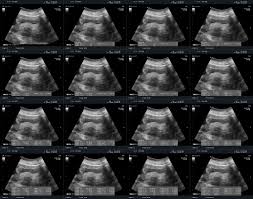

What Are Uterine Fibroids Symptoms Treatment Pictures from images.onhealth.com They rarely interfere with pregnancy. Learn about symptoms and signs associated with uterine fibroids. Uterine fibroids are almost never cancerous, and they don't increase your risk for getting other types of cancer. Uterine fibroids are a common type of noncancerous tumor that can grow in and on your uterus. Reviewed by nivin todd, md on november 08, 2020. Menstrual problems and abnormal vaginal bleeding is the most common symptom of uterine fibroids. Many women over 35 have fibroids, but usually have no. • preservation of uterine artery flow is desired so that the normal myometrium, which is not involved with fibroids, continues to receive blood.

Uterine Fibroids Office On Women S Health from owh-wh-d9-prod.s3.amazonaws.com The most common symptoms of uterine fibroids include Eventually, after many types of research, medical science has concluded that uterine fibroids are the result of hormonal activity, family history, and. Uterine fibroids are noncancerous tumors in the uterus. Uterine fibroids are almost never cancerous, and they don't increase your risk for getting other types of cancer. This is so much applicable. Fibroids are the most common indication for a hysterectomy 7). Uterine arteries with embolic particles, which block blood flow to the fibroids and cause fibroids to shrink. Very rarely do uterine fibroids become cancerous.

Fibroids Guide Causes Symptoms And Treatment Options from www.drugs.com How big can they get? Fibroid tumors are benign by definition. What complications can occur with fibroids ? Uterine fibroids are noncancerous tumors in the uterus. The owh also say that cancerous fibroids are that said, the resolution of symptoms is highly variable depending on the location and size of fibroids. Many women over 35 have fibroids, but usually have no. They grow very slowly and tend to shrink after menopause when levels of. A woman can have many uterine fibroids of different sizes.